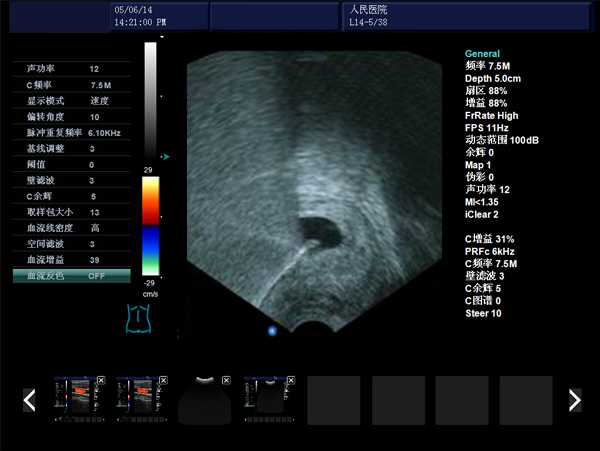

DW-480全數字超聲婦產科手術監視儀

DW-480

產品性能

高集成數字式

寬頻探頭,頻率范圍從2.0MHz到10.0MHz

強勁的組合式模塊化軟件設計

全數字式大容量圖像存貯和文件歸檔管理

操作系統簡單靈活

探頭與陰道窺器相結合,不進入宮腔,不占手術宮頸空間,手術更方便

實時動態高線密度超大角度掃描,有效提升橫向分辨力和側向分辨力、圖像自然更清晰

采用大容量電影回放,實時精微顯示等全數字圖像處理技術,宮腔內部圖像清晰可辨,不容錯過一點殘留,手術干凈徹底,避免了吸宮不全、漏吸等并發癥的發生